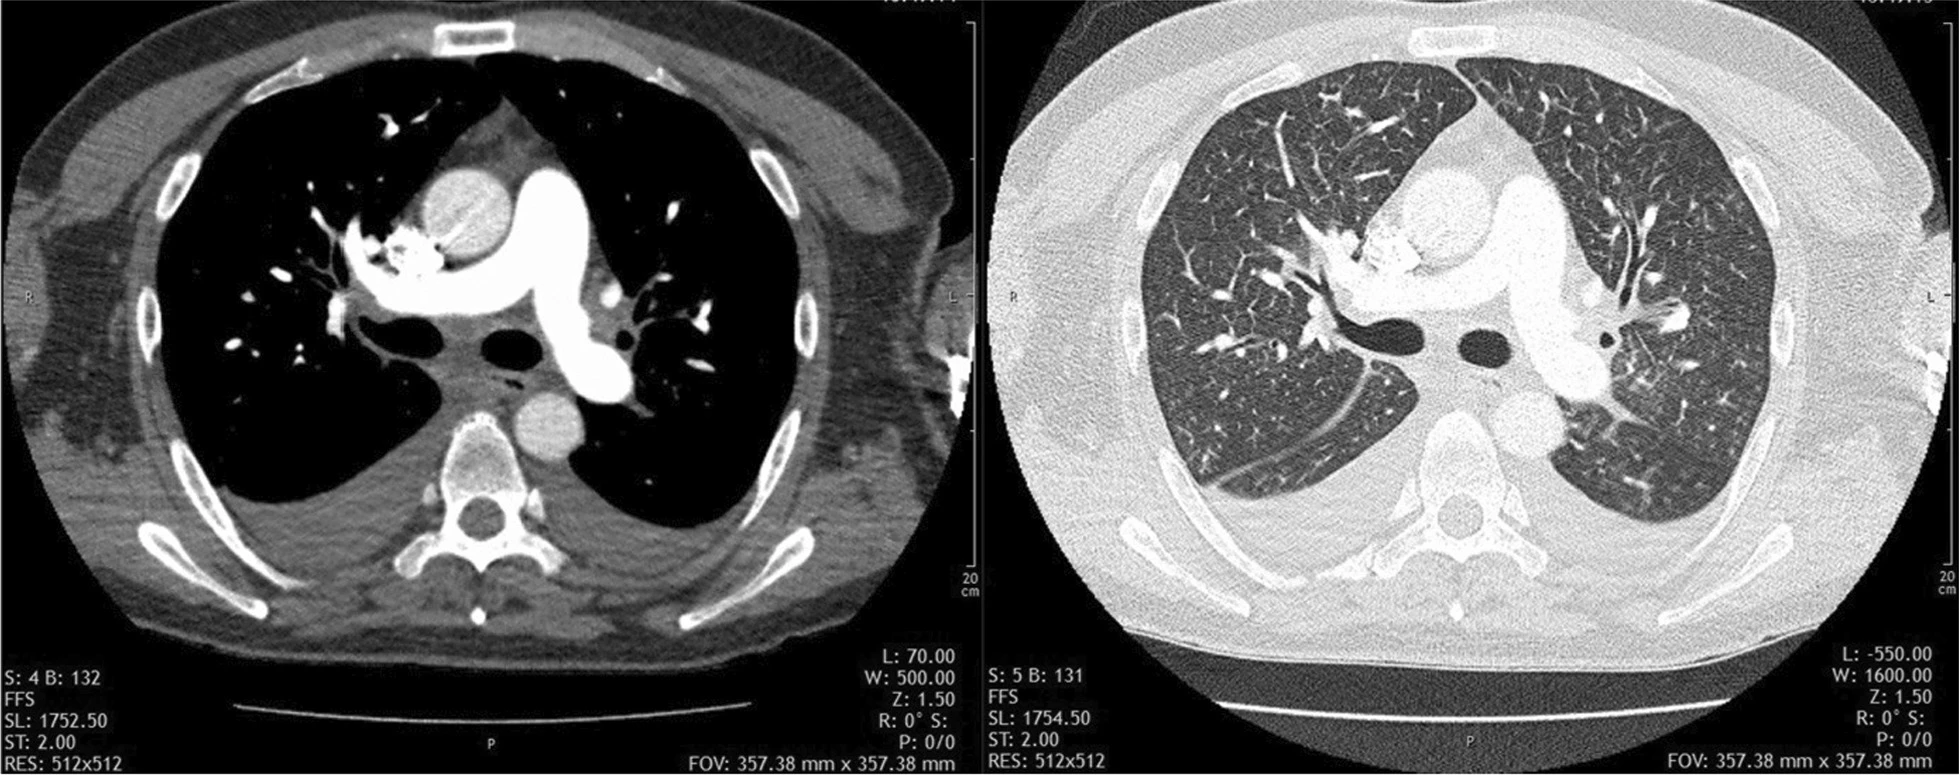

Você atende um caso de uma paciente de 52 anos, do sexo masculino, com tosse crônica, evoluindo com dispnéia aguda. Queixava-se também de dor abdominal e perda de peso, estimada em 8 kgs nos últimos 8 meses¹.

Ao fim do atendimento, você formula muitas hipóteses diagnósticas: tromboembolismo pulmonar (TEP), edema pulmonar, pneumonia, metástases, pneumotórax e derame pleural.... E solicita um exame de angiotomografia computadorizada com protocolo para TEP para te auxiliar na condução do caso.

Embora o exame de angiotomografia com protocolo TEP não tenha confirmado um diagnóstico, ele auxiliou a excluir algumas hipóteses:

- Não haviam sinais de tromboembolismo pulmonar

- Não se observavam focos de consolidação sugestivos de pneumonia

- Não haviam sinais de pneumotórax

- Não se observavam nódulos pulmonares sugestivos de metástases

Frequentemente, um exame radiológico não consegue confirmar um único diagnóstico, mas fornece informações complementares para que o médico assistente possa excluir algumas hipóteses e corroborar outras.